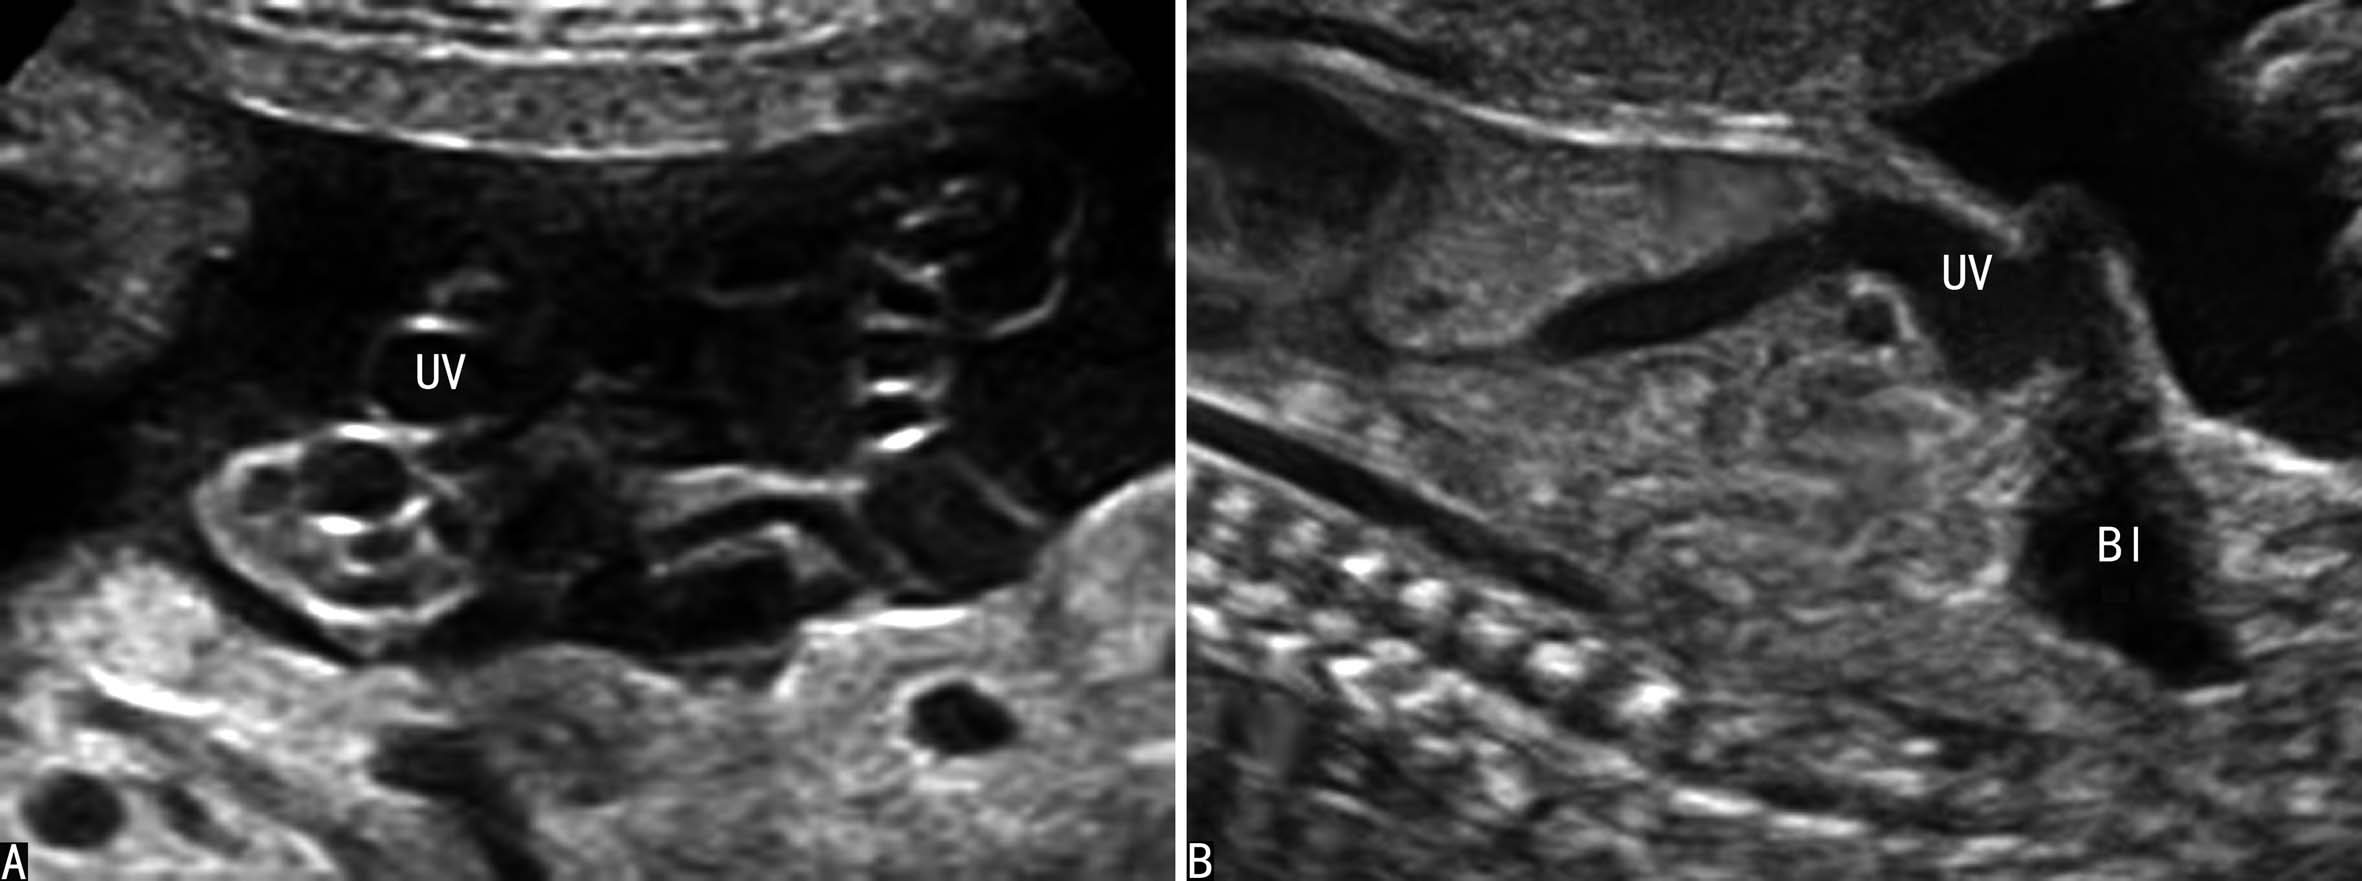

胚胎4周末右脐静脉开始闭锁,第7周时消失,形成正常的左脐静脉循环(图7A)。如右脐静脉不闭锁退化而左脐静脉闭锁,右脐静脉经过肝脏与静脉导管相连进入静脉导管,或绕过肝脏直接与下腔静脉或右心房相连(图7B),形成持续性右脐静脉7。在Hill等1994年进行的回顾性分析中,在15237例产科超声检查中发现了33例PRUV,产前超声检查显示率为0.21%(1:476);其中有18.2%(6/33)的伴有严重的先天性发育异常;在另一篇研究报道中,研究者在低风险胎儿中发现PRUV为1:526,其中17例胎儿合并其他部位的畸形,包括无脑儿、复杂性心脏畸形、双侧唇裂、孤立肾、单脐动脉等。

胎儿腹部横切面显示胃泡和脐静脉以后观察胆囊的位置可以确定脐静脉走行。正常脐静脉穿过脐轮后走行于胆囊的左侧,在胆囊与胃腔之间可以显示脐静脉的回声(图8A);如果在胆囊右侧显示脐静脉回声即可明确右脐静脉的诊断((图8B));肝内型持续性右脐静脉进入肝脏后PRUV需要转向左侧与静脉导管连接(图9)。连续追踪扫查如果显示脐静脉周围或一侧无肝脏实质,则提示为肝外型持续性右脐静脉。一般认为,后者常合并其他部位的发育异常,并可以合并染色体异常。

图8 正常脐静脉与持续性右脐静脉声像图比较